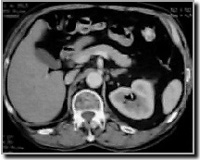

CT-scan van het abdomen of het kleine bekken

Een CT-scan van het abdomen of het kleine bekken wordt genomen om eventuele problemen ter hoogte van de darmen, lever, nieren, milt, enz… te beoordelen.

Ook hier is het van groot belang dat de patiënt tijdens het onderzoek niet beweegt. Er zal een aantal keren gevraagd worden om de adem op houden. Dit is eveneens belangrijk om een goede continuïteit van de beelden te garanderen.

Behalve wanneer het onderzoek wordt gedaan om een beeld te krijgen van de bloedvaten en de beenderstructuren, wordt in principe altijd contrast gegeven om te drinken. Intraveneus contrast wordt toegediend behalve bij beenderonderzoeken.